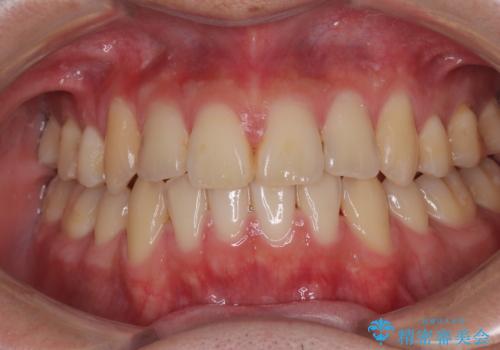

- 高校生の時に行った抜歯矯正の後戻りを気にして来院された患者様です。

インビザラインでの治療を希望されていて、デコボコの程度が中等度であり、安価なパッケージにて対応可能と判断されたため、インビザライン・モデレートを用いて矯正治療を行うこととしました。